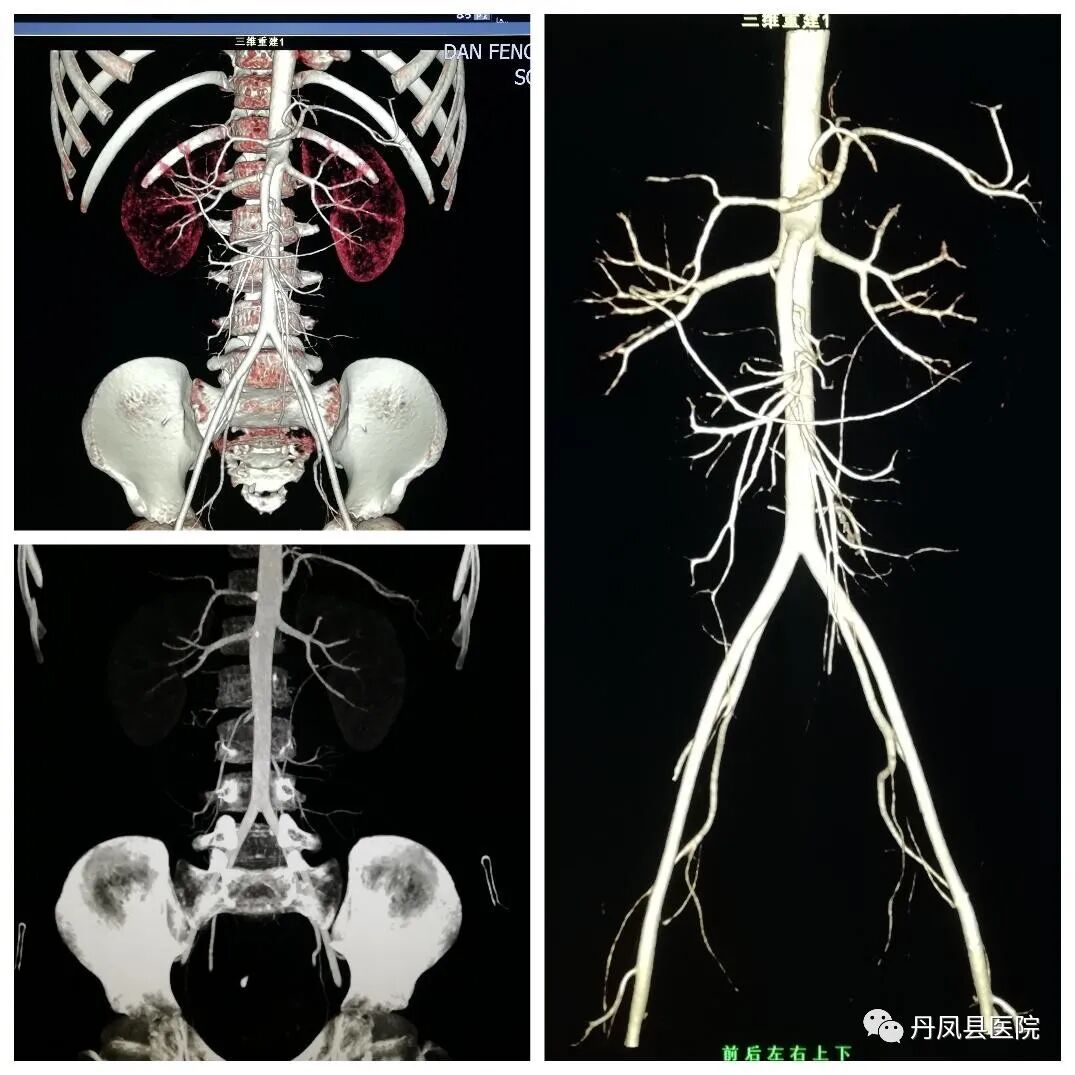

![]()

腹腔干、肠系膜上下动脉CT血管造影(CTA)

头颈部血管CTA

头颈部血管CTA是近年来发展较快的非创伤性血管造影技术,其在诊断颈部、脑血管病变、畸形等方面均显示了无可比拟的优越性,CTA在显示大脑前、中、后及前交通动脉方面敏感性可达89%~100%,该检查无动脉损伤及卒中风险,可很好显示血管壁钙化,能旋转360度,多方位、多角度对血管进行观察,避免血管重叠的干扰,可清晰显示颈内动脉、椎动脉起始段的钙化、扭曲和狭窄。普通放射

普通放射开展常规各部位DR摄影检查、床旁摄影、C型壁术中透视摄影,食管造影、上消化道造影、结肠造影、全消化道造影、静脉尿路造影、膀胱尿道造影、子宫输卵管造影、T型管造影、各类窦道造影及四肢全长、脊柱全长拼接摄影检查。![微信图片_20210419163637.jpg]()

脊柱全长拼接、双下肢全长拼接